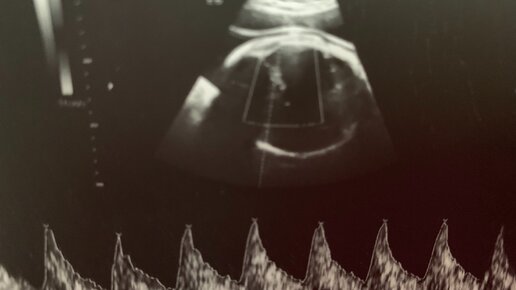

Во время беременности, по мере роста, плод должен занимать в матке определенное положение, которое будет наиболее удобным для того, чтобы малыш в дальнейшем благополучно родился. Это обычно вниз головкой, и определенным образом повернувшись головкой и спинкой, поджав ножки и ручки к телу. Это необходимо, чтобы пройти узкое материнское тазовое кольцо самыми минимальными размерами, как головки, так и плечиков с остальным телом. Но, иногда во время беременности при очередном осмотре и УЗИ-исследовании...

Задержка роста плода — осложнение беременности, проявляющееся в отставании роста плода от нормативных значений. К сожалению, я достаточно часто встречал излишнюю диагностику этого заболевания. «Врач на УЗИ сказал, что ребёнок на неделю отстаёт…». «Мне сказали, что ребёнок должен весить 2000 г, а он сейчас весит 1850…». Давайте разберёмся, как правильно диагностировать ЗРП и почему иногда диагноз поставлен ошибочно. Во-первых, для правильной диагностики ЗРП необходимо точно знать срок беременности, рассчитанный по первому дню последней менструации и первому скринингу (см...